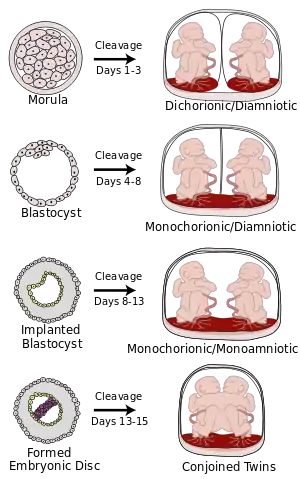

Monochorionic twins are monozygotic (identical) twins that share the same placenta. If the placenta is shared by more than two twins (see multiple birth), these are monochorionic multiples. Monochorionic twins occur in 0.3% of all pregnancies.[1] Seventy-five percent of monozygotic twin pregnancies are monochorionic; the remaining 25% are dichorionic diamniotic.[2] If the placenta divides, this takes place before the third day after fertilization.[2]

Monochorionic twins generally have two amniotic sacs (called Monochorionic-Diamniotic "MoDi"), but sometimes, in the case of monoamniotic twins (Monochorionic-Monoamniotic "MoMo"), they also share the same amniotic sac. Monoamniotic twins occur when the split takes place after the ninth day after fertilization.[2] Monoamniotic twins are always monozygotic (identical twins).[3] Monochorionic-Diamniotic twins are almost always monozygotic, with a few exceptions where the blastocysts have fused.[2]